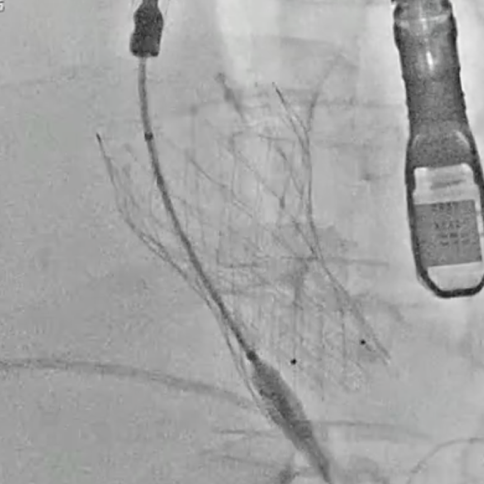

CT评估提示三叶瓣结构,无明显钙化,窦部空间充足;冠脉开口位置安全;主动脉弓角度锐,外周血管走行迂曲,术中释放轴向控制存在挑战。

手术中经右股动脉入路,拟植入VenusA-L 29mm瓣膜。因弓部角度锐利,导丝跨弓两次尝试后成功,造影未见主动脉夹层。最终在超声引导下回收重置,瓣膜同轴性理想,展开良好,反流完全消失,手术顺利完成。

瓣膜过弓

瓣膜释放